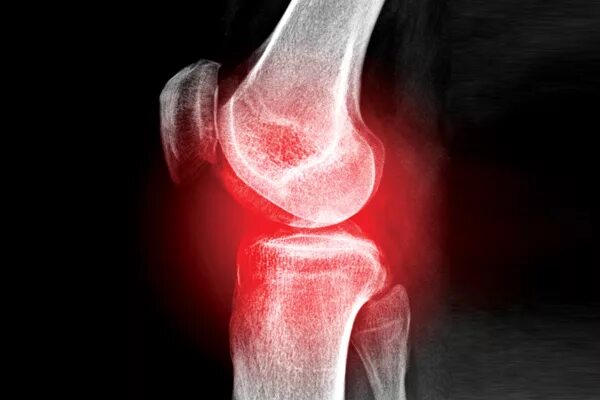

Как лечить ушиб коленного сустава